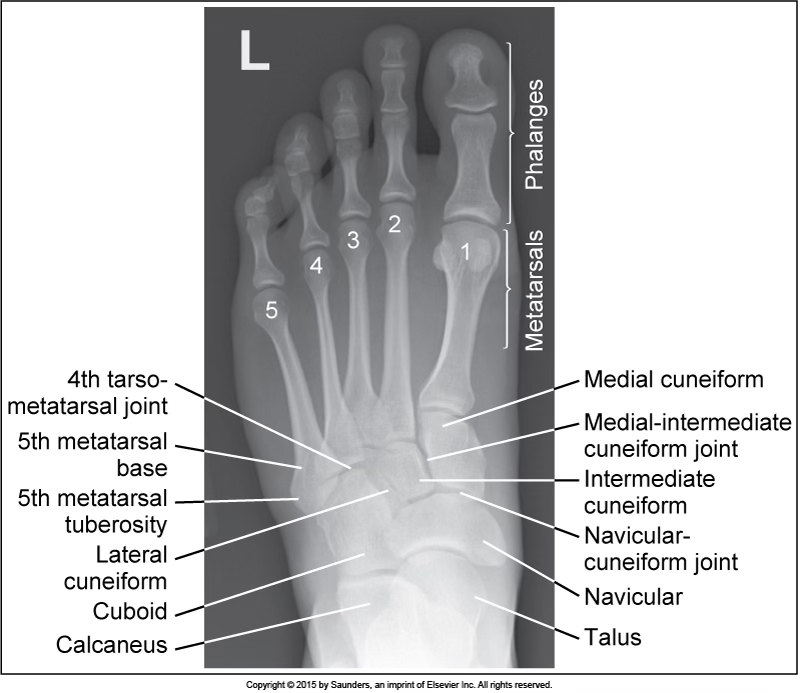

AP axial foot

accurate positioning